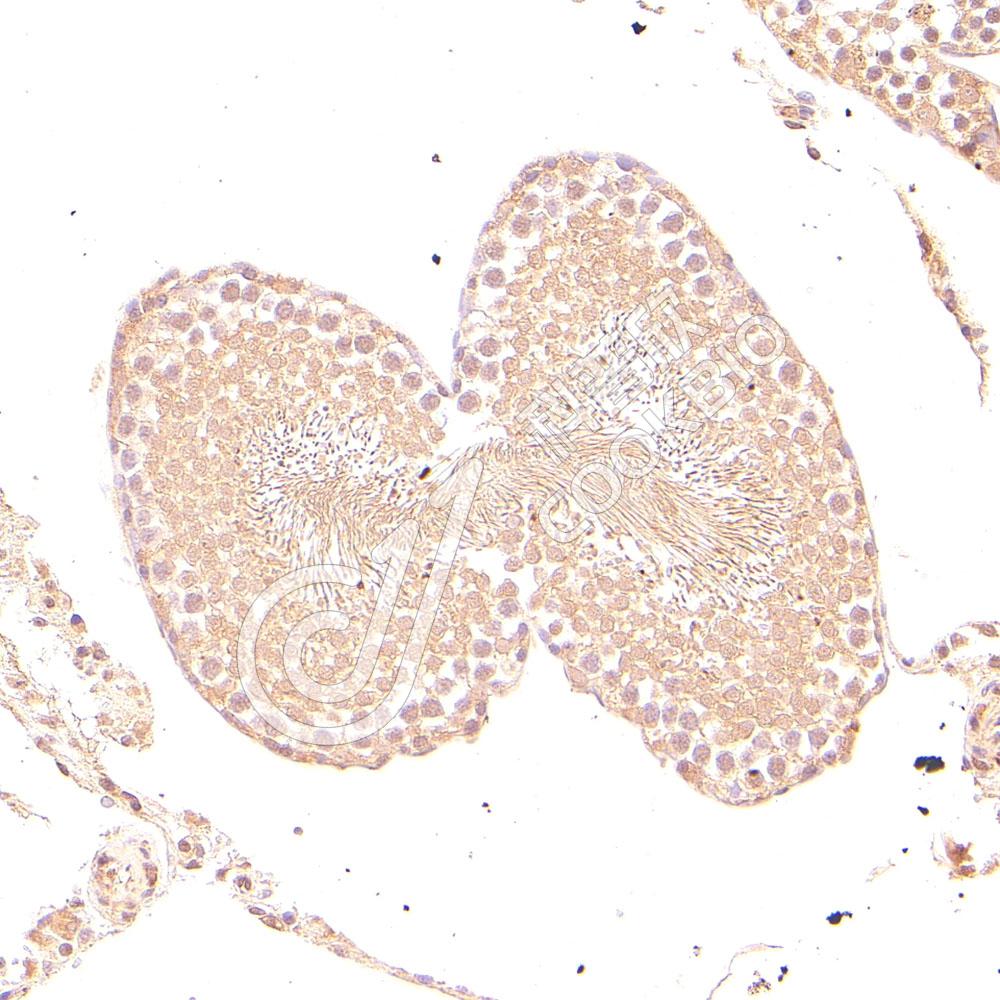

IHC检测IRAK1-binding protein 1蛋白(货号 K1346050).

样品: 小鼠睾丸, 4%多聚甲醛 (货号KSG1101) 固定12-24小时.

抗原修复: Tris-EDTA抗原修复液(pH 9.0) (KSG1203), 98℃, 20分钟.

—抗: 1: 1500稀释, 4℃ 孵育过夜.

二抗: S-vision免疫组化多聚二抗(山羊抗兔),即用型 (货号KB3906), 室温孵育20分钟.

样品: 大鼠睾丸, 4%多聚甲醛 (货号KSG1101) 固定12-24小时.